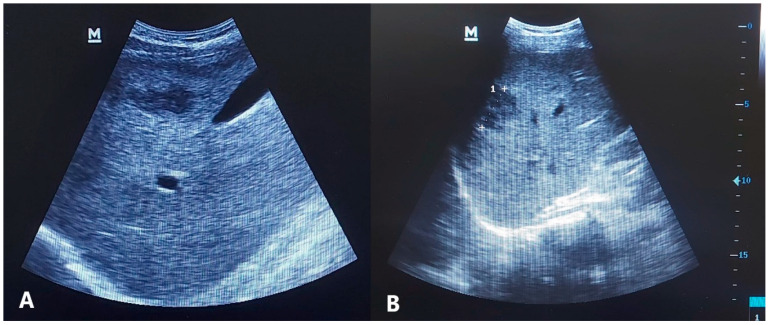

三氯苯达唑(TCBZ)是治疗片形吸虫病的金标准。然而,关于耐药性的报道越来越多,强调了替代治疗的必要性。TCBZ联合伊维菌素(IVM)治疗动物片形吸虫病疗效显著。在此基础上,我们旨在评估TCBZ/IVM联合治疗人片形吸虫病的疗效。本研究招募了来自上埃及的136例片形吸虫患者,他们被分为第一组(n = 65),接受TCBZ单药治疗,第二组(n = 71),接受TCBZ/IVM联合治疗。评估是基于临床、嗜酸性粒细胞和放射学参数来评估治疗反应。慢性筋膜吸虫病17例(12.5%)。在年龄和性别方面没有观察到差异。两组的所有参数均有显著改善,第二组的效果更明显。联合治疗组有更高的完全缓解,包括临床、嗜酸性粒细胞和放射学的改善,达到53.3%,而单药治疗组为26.2% (p < 0.001)。高基线嗜酸性粒细胞计数与反应显著相关。TCBZ/IVM联合治疗人片形吸虫病的疗效提示可能有促进作用,可以使TCBZ失效的区域受益。需要进一步的大规模随机研究来证实这些发现。

Triclabendazole (TCBZ) is the gold standard treatment for fascioliasis. However, reports on resistance are increasing, emphasizing the need for alternative therapy. Combining TCBZ with ivermectin (IVM) was found to be effective for treating animal fascioliasis. Building on this, we aimed to evaluate the efficacy of the TCBZ/IVM combination therapy for human fascioliasis. This study enrolled 136 patients with Fasciola from Upper Egypt, and they were divided into the first group (n = 65), who received TCBZ monotherapy, and the second group (n = 71), who received the TCBZ/IVM combination. Assessments were to evaluate treatment response based on clinical, eosinophilic, and radiological parameters. Chronic fasciolosis was diagnosed in 17 patients (12.5%). No differences were observed in age and sex. Significant improvements were noted in all parameters in both groups, with more pronounced effects observed in the second group. A significantly higher complete response, including clinical, eosinophilic, and radiological improvements, was reported in the combined therapy group, with 53.3% compared to 26.2% in the monotherapy group (p < 0.001). A high baseline eosinophilic count was significantly associated with response. The efficacy of the TCBZ/IVM combination for treating human fascioliasis suggested a possible boosting effect, which can benefit regions of TCBZ failure. Further large-scale randomized studies are warranted to confirm these findings.